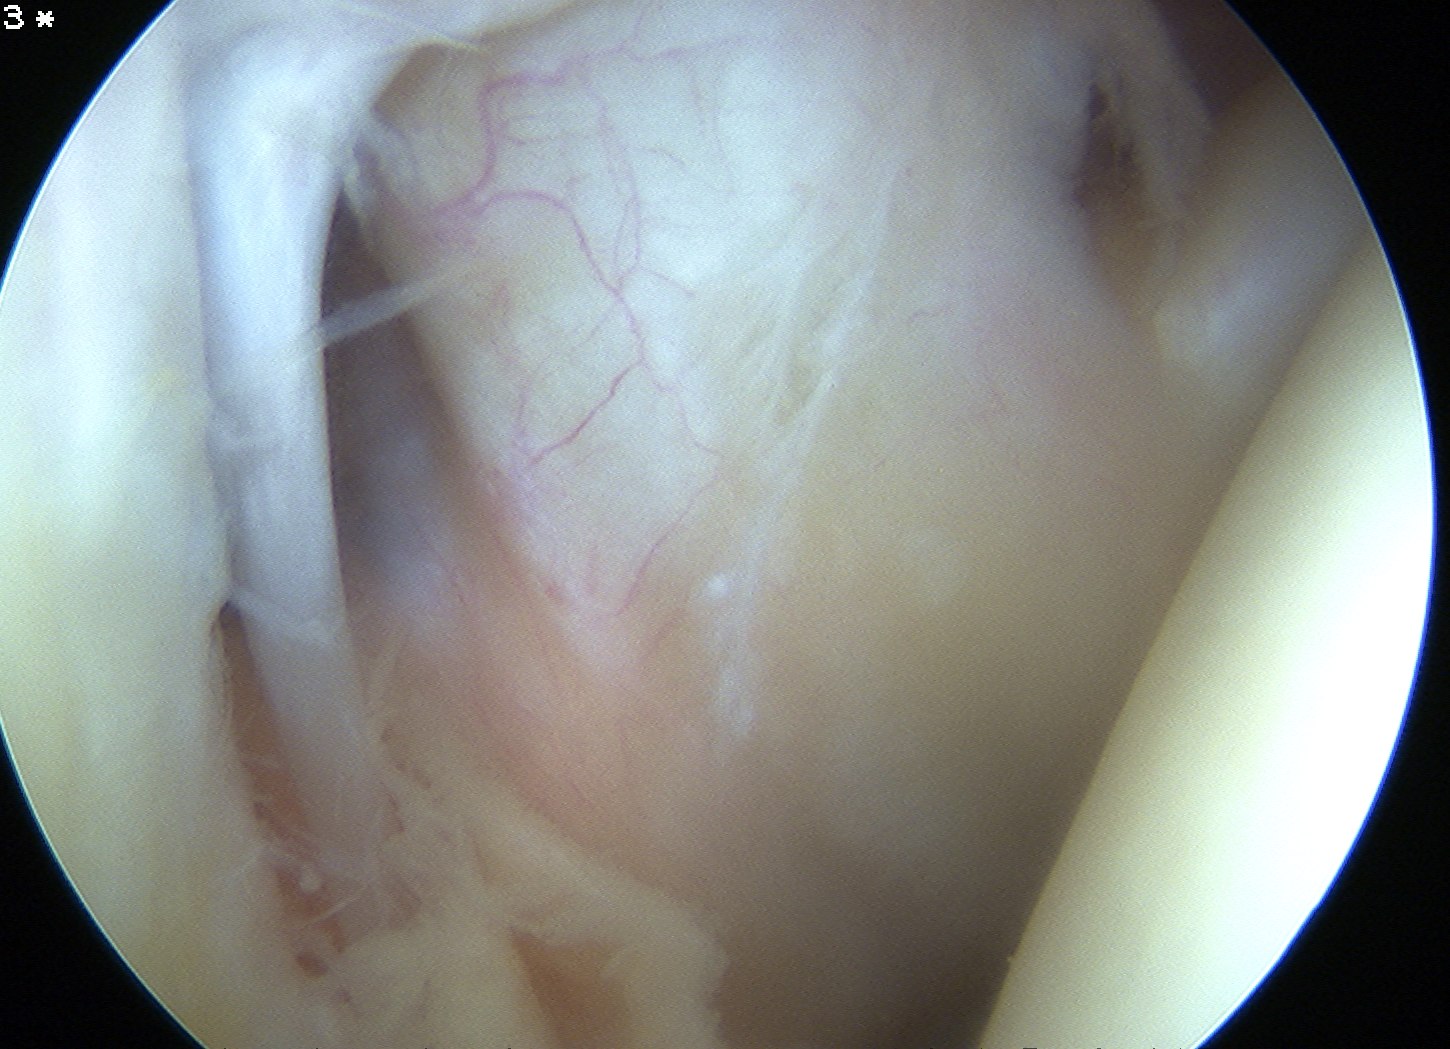

Glenohumeral joint assessment

Labrum

Variations in anterior labral anatomy above equator

| Sublabral foramen | Sublabral foramen with cord like MGHL | Absent labrum with cord like MGHL |

|---|---|---|

| Buford complex | ||

Glenoid assessment

Anterior chondral damage

Anterior glenoid bone loss

Hill Sachs lesion